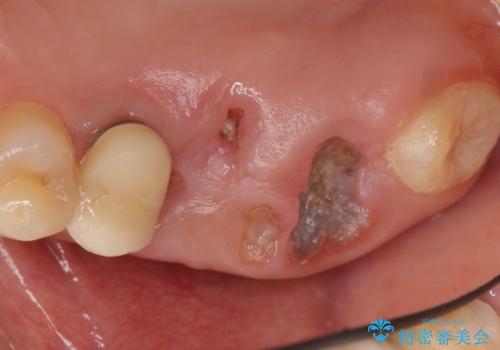

- う蝕により奥歯がボロボロで咬めないことを主訴に来院された患者様です。

奥歯2本(右上76)はう蝕が深く保存不可能な状態であったため、やむなく抜歯しました。

インプラントも入れ歯も抵抗があるとのご相談により、自家歯牙移植を提案しました。